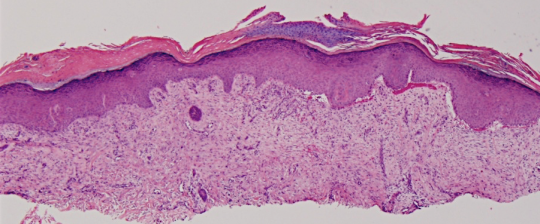

VA38: Upper Forehead, Left of Midline, Actinic Keratosis, Hypertrophic

- Arrows indicate base of epidermal thickening

VA36: Upper Forehead, Left of Midline, Adjacent, Normal